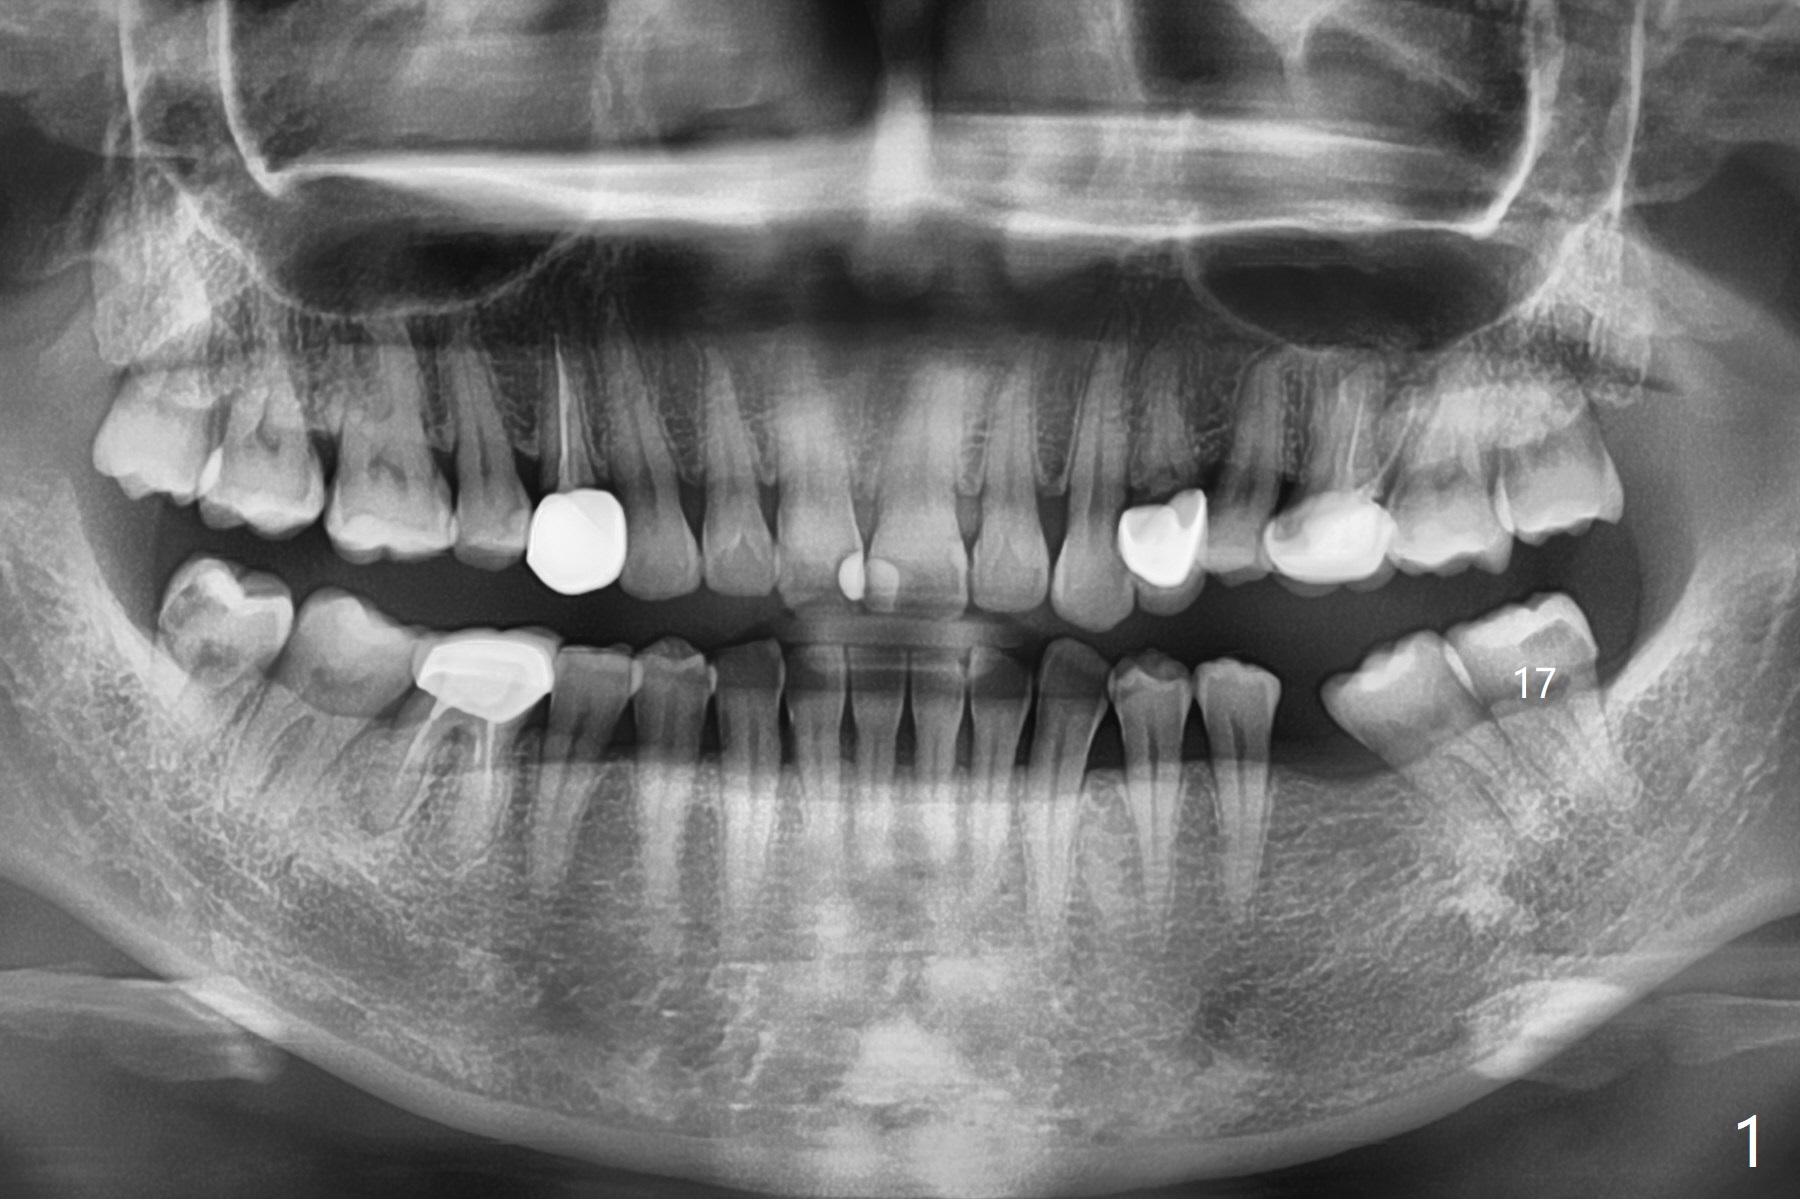

39岁女渴望有一个正常19号牙(图一),第一步,17号牙拔除,粘性骨粉植骨(图二:*),PRF覆盖,树脂敷料。后者术后八天由于倒凹(图三:^),稳定,下面(*)骨粉谅必安居乐业。术后一两个月(伤口愈合,18号牙牙冠远中面充分暴露)后,准备口扫做局部矫正(Clear Aligner),竖直18号牙,植骨有利于18号牙进入17号牙牙槽窝。然后再口扫制作19号牙种植导板。